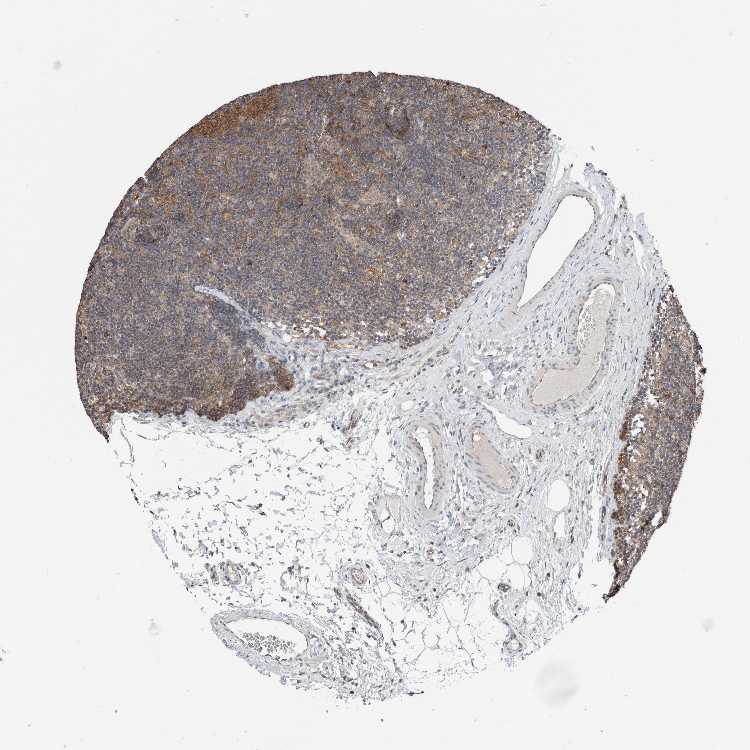

TISSUE PRIMARY DATA LYMPH NODE Show tissue menu

Lymph node

LYMPH NODE - Expression summary

LYMPH NODE - Antibody stainingi

Antibody staining in the annotated cell types in the current human tissue is reported as not detected, low, medium, or high, based on conventional immunohistochemistry profiling in selected tissues. This score is based on the combination of the staining intensity and fraction of stained cells.

Each image is clickable and will lead to virtual microscopy that enables deeper exploration of all samples and also displays staining intensity scores, fraction scores and subcellular localization as well as patient and tissue information for each sample.

Antibody HPA030419Antibody HPA030420Antibody HPA030422Antibody CAB025196Antibody CAB080286Antibody CAB080287

Germinal center cells Not detectedNot detectedLowHighHighMedium

Non-germinal center cells Not detectedNot detectedLowMediumMediumLow